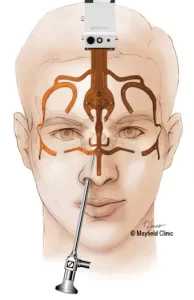

جراحی تومور هیپوفیز از طریق بینی (رویکرد ترانسفنوئید): روش انجام و مزایا

جراحی تومور هیپوفیز یکی از پیشرفتهترین و کمتهاجمیترین روشهای جراحی مغز و اعصاب است که از طریق بینی انجام میشود. در این روش، جراح بدون